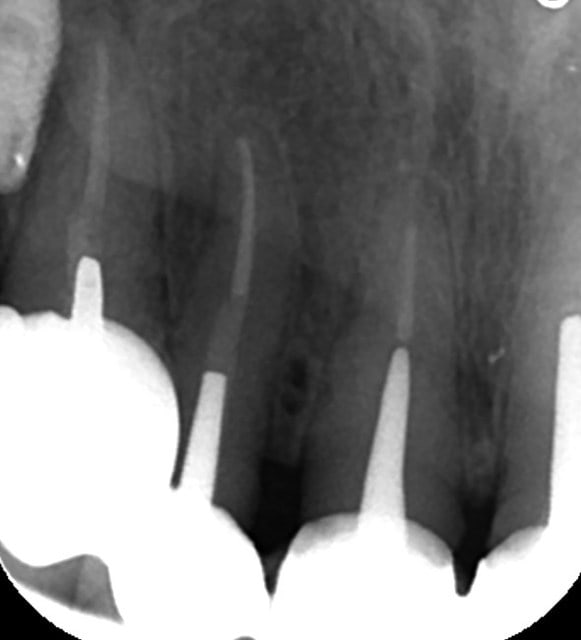

bon, suite...

je viens d'avoir les images...

autant sur la 11 çà paraît jouable...autant sur la 12 je pense que c'est mort!!!

faux canal, il ne reste quasi plus rien de la partie vestibulaire de la dent...

point positif: il semblerait que j'ai encore de quoi ancrer une vis sous les fosses nasales en apical de cette 12...

donc amha çà sent l'EII avec mise en vitrine immédiate...et si c'est le cas, je ne ferai pas de quartier à la 11...elle passera elle aussi à la trappe vu le risque de récidive et/ou de contamination du biomat qu'il me faudra mettre pour éviter que tout ne s'effondre...